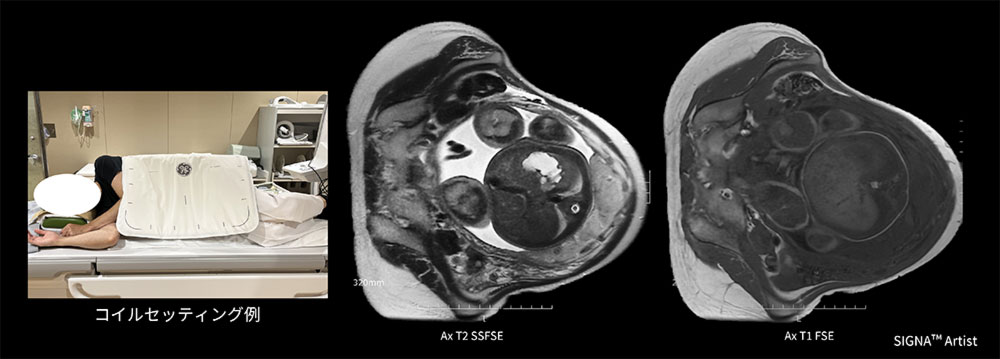

Case2 妊婦の子宮胎盤検査

30代の妊婦。重複子宮の疑いにて経腟分娩可能か評価する目的にてMRI検査を実施。

検査時35週で推定胎児体重が2384gであり、本人より仰臥位困難の訴えがあったため、側臥位でAIR™ Coilの向きを変えて腹部全体にコイルを覆いポジショニングを行った。側臥位にすることで患者さんの負担も少なくセッティングもスムーズで検査が施行でき、出産方法の決定に貢献できた一例(図4)。

AirCoils_Shigaikadai_05.jpg

図4 妊婦の子宮胎盤検査におけるAIR™ Coilのセッティング例と臨床画像